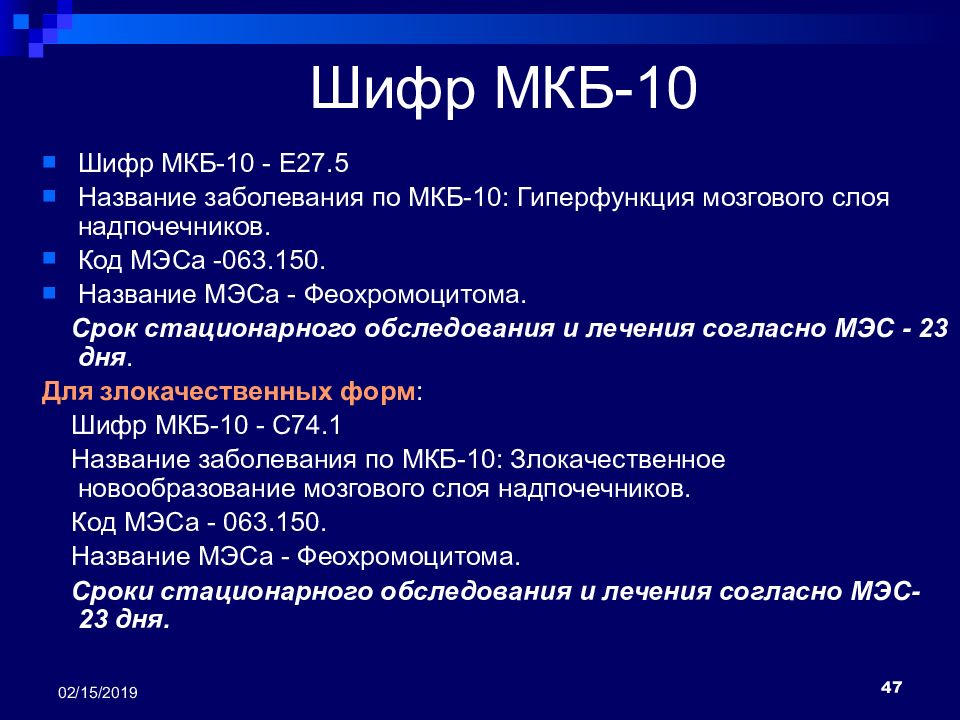

Код мкб 10 атерома головы

Код мкб 10 атерома головы 109 фото